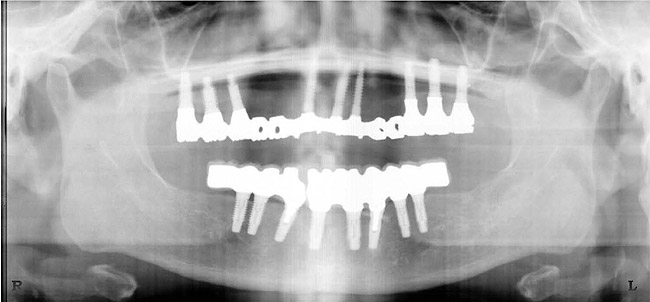

Fixed Restorations: Large Segment/Full Arch

For large-segment/full-arch fixed prostheses, the critical distance is 15 mm. If the distance from the implant platform to the occlusal table is less than 15 mm, then the prosthetic material indicated is porcelain-fused-to-metal (PFM) (Figure 3). If the distance is greater than 15 mm, then a hybrid prosthesis should be used (Figure 4).

The 15-mm measurement is important because of the physical properties of the restorative materials. Acrylic requires bulk for strength. If there is less than 15 mm of distance from the implant platform to the occlusal table, there will not be sufficient space to achieve the bulk of acrylic necessary to provide strength for the prosthesis. The unfortunate result will be continual repair of fractures for the life of the prosthesis.

Likewise, PFM restorations have difficulties when too much space is available. At dimensions greater than 15 mm from the implant platform to the occlusal table, the control of surface porosity across the metal substructure becomes difficult because of variations in cooling and heating rates across the metal,10 which in turn makes it difficult to bake porcelain to the metal substructure. The result is the high possibility of future unwanted complications of porcelain fracture.11

There is also a considerable difference in the laboratory costs for these types of prostheses. A PFM restoration requires more metal to achieve a uniform 2-mm thickness and is more technique-sensitive (Figure 5 and Figure 6). A hybrid prosthesis requires less metal and uses acrylic and denture teeth for the remaining restoration (Figure 7 and Figure 8). Understanding the impact that the 15-mm height has on which type of restoration is required gives the dentist the ability to quote a more accurate fee to the patient.

Figure 3   A crown height space < 15 mm necessitates a PFM material selection.

Figure 3

Figure 4  A crown height space > 15 mm necessitates a hybrid restoration.

Figure 4

Figure 5  The increased amount of metal required for this prosthesis greatly increases the laboratory costs.

Figure 5

Figure 6  The increased amount of metal required for this prosthesis greatly increases the laboratory costs.

Figure 6